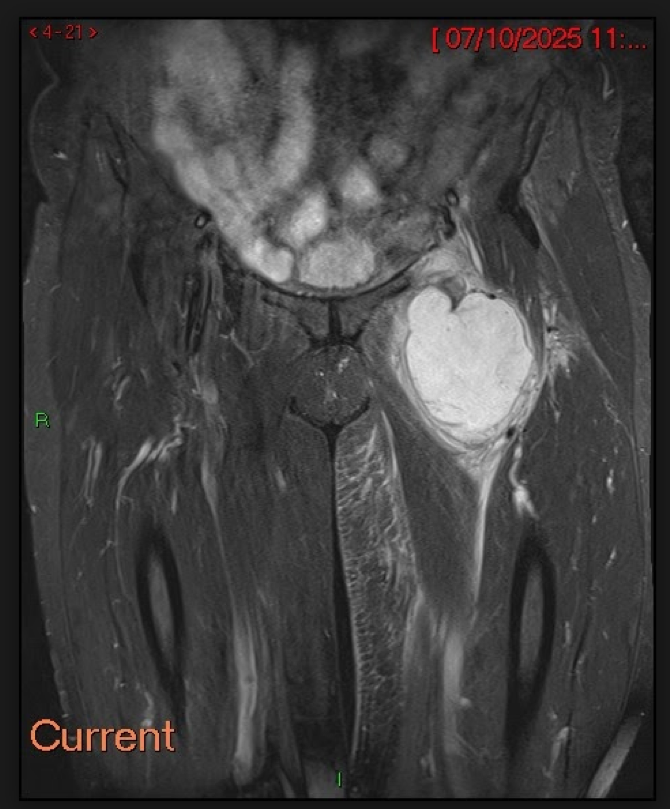

Fig.07. MRI Pelvis with post-Gadolinium enhanced T2-weighted sequences. Post-contrast images reveal marked circumferential enhancement of the lesion's nodular soft-tissue components. There is a large central region of high signal intensity consistent with intra-tumoural necrosis.

Fig.08. Post-contrast T2-weighted MRI Pelvis with post-Gadolinium enhanced T2w sequences. Post-contrast images reveal marked circumferential enhancement of the lesion's nodular soft-tissue components. There is a large central region of high signal intensity consistent with intra-tumoural necrosis.